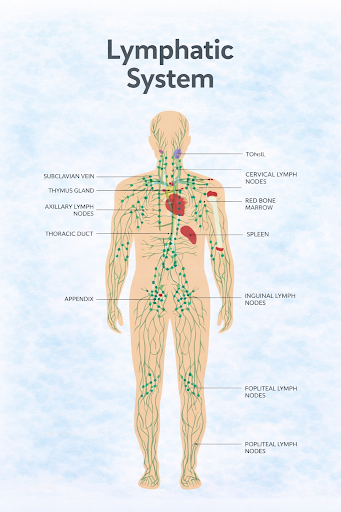

What are Blood Cancers and Lymphomas?

Blood cancers are a group of cancers that affect the blood, bone marrow, or lymphatic system. Lymphomas are a type of blood cancer that primarily involves the lymphatic system, which plays an important role in immunity. These cancers occur when certain blood-forming or immune cells begin to grow and behave abnormally.

Blood cancers are a group of cancers that affect the blood, bone marrow, or lymphatic system. Lymphomas are a type of blood cancer that primarily involves the lymphatic system, which plays an important role in immunity. These cancers occur when certain blood-forming or immune cells begin to grow and behave abnormally.

Where It Begins

Blood cancers and lymphomas may begin in:

Because these systems are interconnected, abnormal cells may circulate or appear in multiple areas.

- Bone marrow, where blood cells are produced

- Bloodstream, which carries cells throughout the body

- Lymphatic system, including lymph nodes, spleen, thymus, and lymph vessels

Because these systems are interconnected, abnormal cells may circulate or appear in multiple areas.

Lymphoma: Types and Staging

Types of Lymphoma

There are two main types:

Hodgkin Lymphoma

Characterised by the presence of a specific abnormal cell type.

Non-Hodgkin Lymphoma

A larger group with many subtypes that vary in how they grow and respond to treatment.

Lymphomas may also be described as:

Staging of Lymphoma

Lymphoma is staged based on how far it has spread within the body:

Lymphoma: Types and Staging

Types of Lymphoma

There are two main types:

Hodgkin Lymphoma

Characterised by the presence of a specific abnormal cell type.

Non-Hodgkin Lymphoma

A larger group with many subtypes that vary in how they grow and respond to treatment.

Lymphomas may also be described as:

- Slow-growing (indolent)

- Fast-growing (aggressive)

Staging of Lymphoma

Lymphoma is staged based on how far it has spread within the body:

- Stage I – Involvement of a single lymph node region or site

- Stage II – Involvement of two or more regions on the same side of the diaphragm

- Stage III – Involvement on both sides of the diaphragm

- Stage IV – Spread to organs outside the lymphatic system